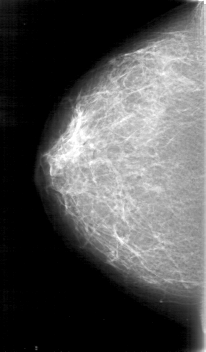

D_4075_1.LEFT_MLO

FILE: D_4075_1.LEFT_CC.OVERLAY

TOTAL_ABNORMALITIES 1

ABNORMALITY 1

LESION_TYPE MASS SHAPE LOBULATED MARGINS CIRCUMSCRIBED

ASSESSMENT 0

SUBTLETY 5

PATHOLOGY BENIGN

TOTAL_OUTLINES 1

BOUNDARY